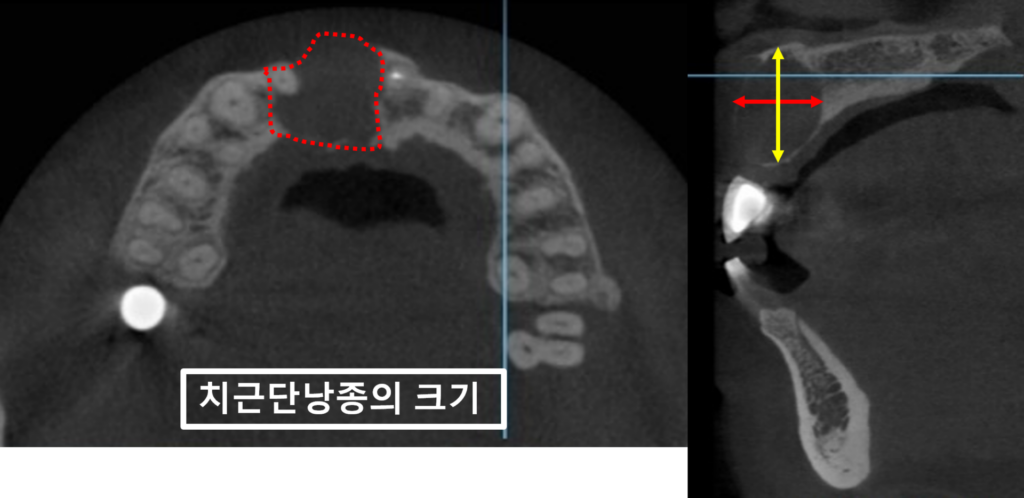

입안물혹을 제거하기 위해

촬영한 CT 사진입니다.

빨강색점선을 보시면 횡방향으로

치아뿌리물혹이 얼마나 큰지 알 수 있습니다.

빨강색화살표와 노랑색화살표는

거대 치근단낭종의 대략적인 크기를 보여줍니다.

노랑색화살표 끝이 코 끝입니다 !!!